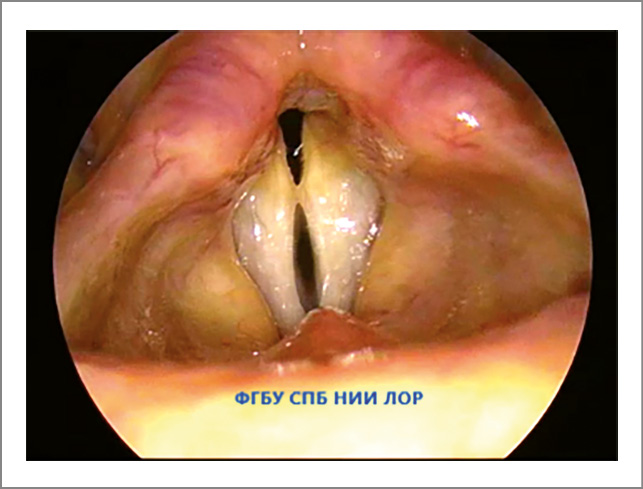

- Фонационная щель пациентов с функциональной дисфонией не соответствует форме фонационной щели здоровых людей. Изменение формы фонационной щели – основной признак гипотонуса голосовых складок. Сниженный тонус мышц гортани проявляется овальной, широкой линейной или треугольной фонационной щелью. Если у пациентов с функциональной дисфонией форма фонационной щели напоминает овал, то это свидетельствует о преимущественном снижении тонуса голосовых мышц (рис. 1). При снижении тонуса межчерпаловидных мышц фонационная щель имеет вид треугольника с верхушкой в передней комиссуре и основанием в межчерпаловидной области (рис. 2).

Рис. 1. Функциональная дисфония по гипотонусному типу (фонация): овальная щель.